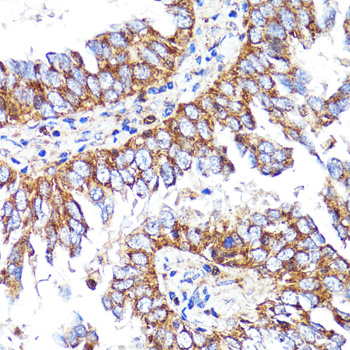

| Application: | WB IHC |

| Application: | WB IHC |

| Recommended Dilution: | WB 1:500 - 1:2000 IHC 1:50 - 1:100 |